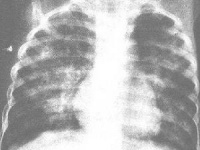

X线胸片可见云絮状斑片影,大小、形状及位置都不恒定,呈游走样,于短期内消失及另一部位再发。偶见双肺弥漫颗粒状阴影需与粟粒性肺结核鉴别。